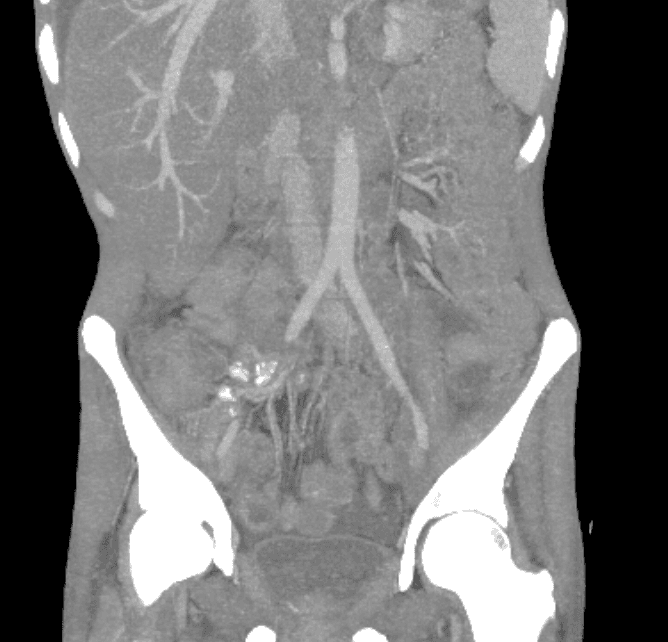

Prior abdominal imaging at an outside hospital reportedly showed extensive abdominal and pelvic lymphadenopathy with mass-like thickening of the terminal ileum and cecum, raising concern for malignancy. He declined admission at that time. Symptoms progressed as he developed worsening abdominal pain, fatigue, and ongoing diarrhea, prompting emergency evaluation.

Abdominal CT